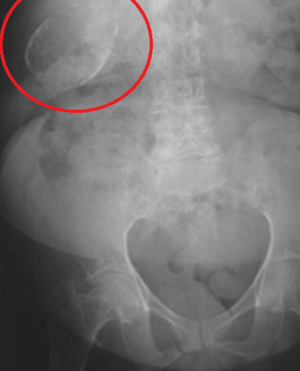

Porcelain gallbladder

Porcelain gallbladder on X-ray | |

Porcelain gallbladder is a calcification of the gallbladder believed to be brought on by excessive gallstones, although the exact cause is not clear. As with gallstone disease in general, this condition occurs predominantly in overweight female patients of middle age. It is a morphological variant of chronic cholecystitis. Inflammatory scarring of the wall, combined with dystrophic calcification within the wall transforms the gallbladder into a porcelain-like vessel. Removal of the gallbladder (cholecystectomy) is the recommended treatment.

Abdominal radiography (X-ray), abdominal ultrasound or CT scan.